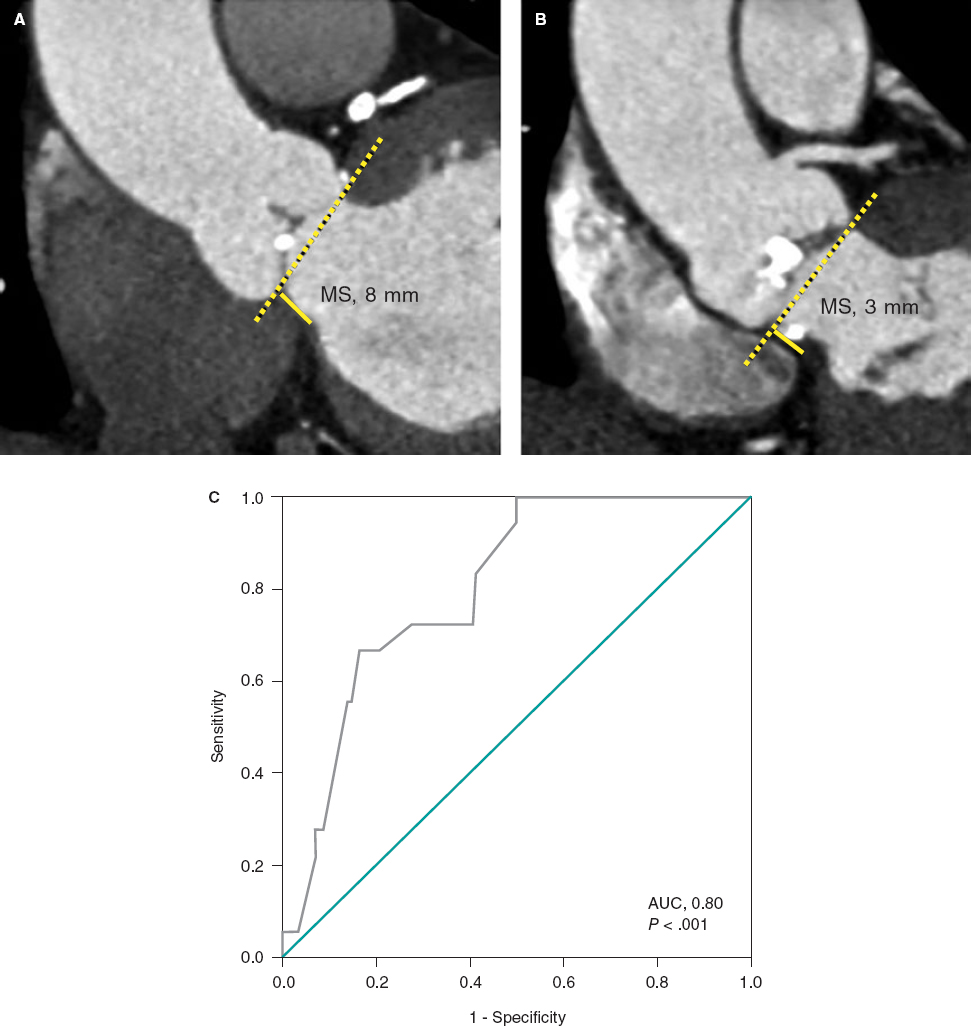

Diagnostic study of a CTO

The rate of success is associated with a good diagnostic study to determine the vessel architecture in the occlusion region. It is important to locate the occlusion proximal edge and see if there are microchannels or proximity collaterals, but we do not need to use more than 15 images per second; however, at times it is necessary to increase the volume and pressure of contrast injection. The catheters should be perfectly placed inside the coronary ostia to avoid losing contrast through the aorta. Contralateral injections are also crucial (sometimes collateral circulation is homolateral) to see the occlusion final edge, the anatomy of the distal bed, make correct assessments of the collaterals, and determine whether the retrograde interventional procedure is possible.

There is a special situation when the anterior descending artery receives collateral circulation through Viuessens’ arterial ring35 where the right conus artery may anastomose with the left conus artery that exits the proximal or medial segment of the anterior descending artery. There are times when this conus artery exits an independent ostium of the right coronary artery and needs to be cannulated using a mammary artery catheter with a specifically curved tip or a hockey stick design. It is advisable to perform a coronary CT scan to evaluate the architecture of the occlusion in patients undergoing aortocoronary revascularization surgery, with high J-CTO scores or aorto-ostial occlusions.